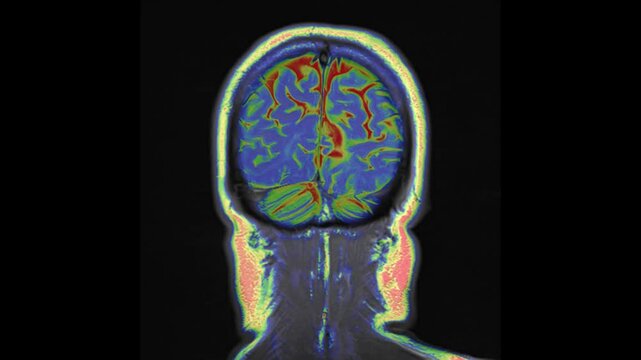

Coloured  coronal view T2-weighted magnetic resonance imaging (MRI) scan of a normal brain.

00:04

coronal view T2-weighted magnetic resonance imaging (MRI) scan of a normal brain.